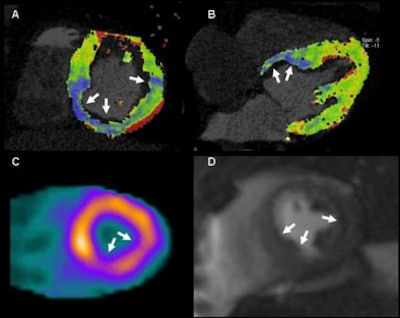

| In a 51-year-old man with suspected coronary artery disease, rest and perfusion CT (above) shows a hypoperfused blue color-coded area inferoseptally, in results that are well-correlated to both SPECT and MRI. In the same patient the results showed delayed contrast enhancement at both CT and MRI, coronary CT angiography revealed calcified plaques in the corresponding coronary artery. |

The researchers examined 30 patients (18 men, 12 women; ages 51-76; mean age, 62 ± 12) using a standardized-protocol triphasic cardiac CT scan that included prospectively electrocardiogram-triggered coronary angiography, dynamic stress myocardial perfusion imaging, and delayed-enhancement imaging. Each patient also underwent stress and rest perfusion MRI, and delayed-enhancement MRI and SPECT, he said.

Scanning with DSCT (Somatom Definition Flash, Siemens Healthcare), the researchers started their imaging sequence three minutes into adenosine stress (regadenoson, 140 µg/kg/min) using a dynamic scanning mode with image acquisition at two automatic table positions and the table shuttling back and forth between the two positions, Weininger explained. Images were acquired at 100 kV and 300 mAs, with a 10% overlap between both acquisition ranges, resulting in 73 mm of anatomic coverage.

The imaging sequence was started four seconds prior to the bolus (50 mL contrast, 50 mL saline chaser at 6 mL/sec flow rate) to ensure a baseline acquisition of noncontrast-enhanced images -- similar to what's done with MRI, Weininger said.

- Qualitatively: visual interpretation of CT perfusion in conjunction with delayed-enhancement CT, MRI, and SPECT

- Semiquantitatively: analysis of short-axis reformats using software (Argus, Siemens), compared to perfusion MRI

- Quantitatively: calculation of myocardial blood flow using prototype software (syngo Volume Perfusion, Siemens)

In the quantitative analysis, CT perfusion correctly classified 54 perfusion defects of the 60 identified by MRI, yielding 86% sensitivity and 98% specificity. At the semiquantitative analysis, the group found significant differences in the upslopes of the signal intensity of the time curve between normal and ischemic myocardium of both CT and MRI, Weininger said. In the absolute quantification of myocardial blood flow, CT was again able to differentiate between normal and ischemic myocardium, he said.